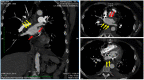

Thromboembolic events have been reported as frequent and fearsome complications in patients affected by SARS-CoV-2 infection. Patients undergoing cardiac valve replacement exhibit an increased risk of valve thrombosis, even with prosthetic biological valves, and especially in the first period after surgery. The management of these patients is challenging and requires prompt interventions. We report the case of a young woman infected by SARS-CoV-2 three months after double cardiac valve replacement that developed a massive prosthetic biological valve thrombosis despite optimal anticoagulant therapy.